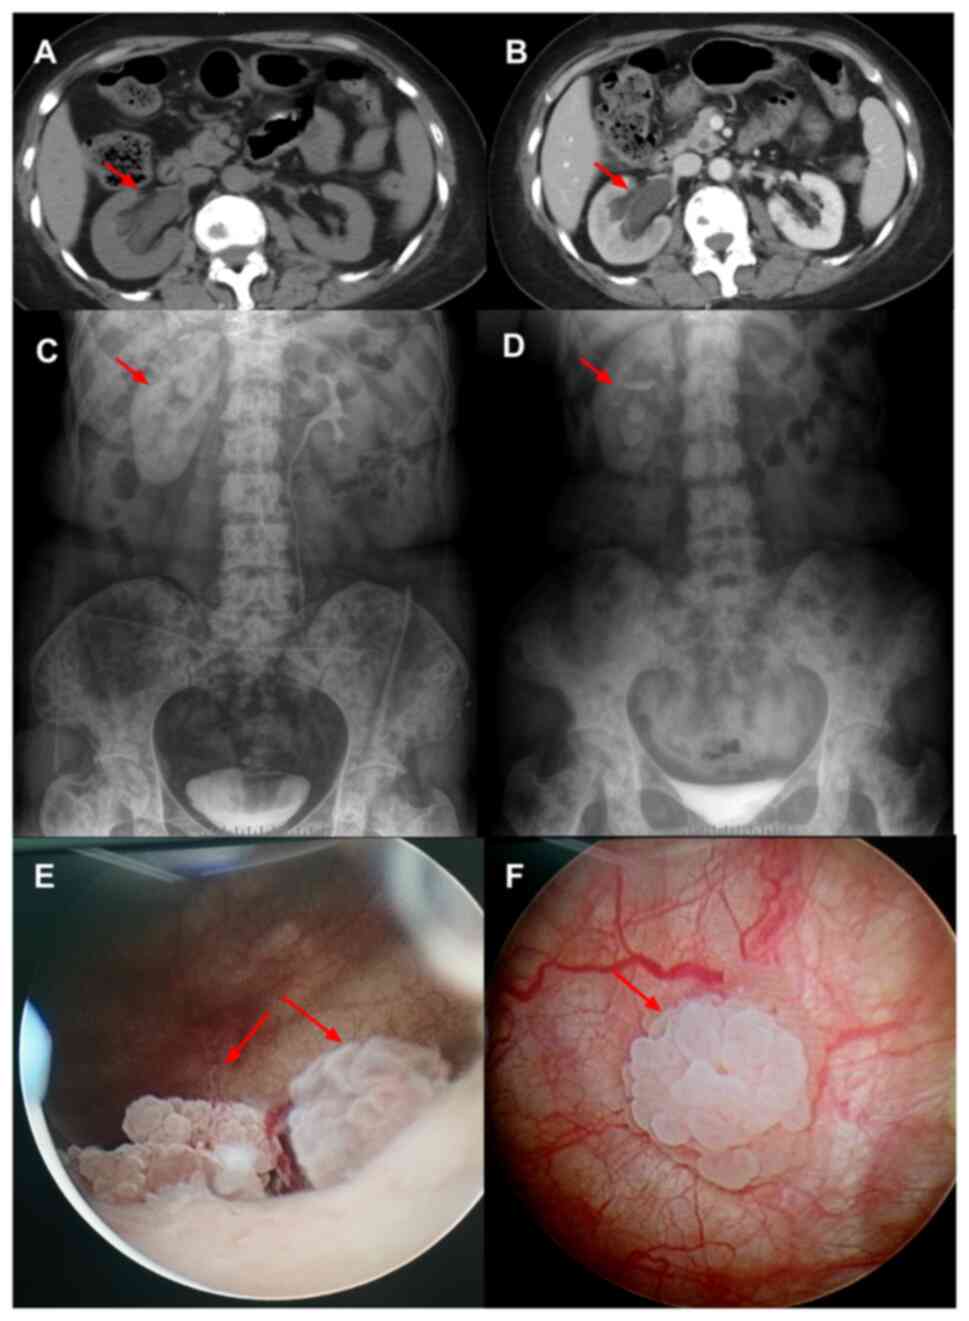

It - Pennywise - Bishoujo Statue - Horror Bishoujo - 1/7, Molecular basis of VEGFR1 autoinhibition at the plasma,

Molecular basis of VEGFR1 autoinhibition at the plasma, Metastasis to the bladder from primary breast cancer: A case,

Metastasis to the bladder from primary breast cancer: A case, Structural Basis for the Calmodulin-Mediated Activation of2017年版ペニーワイズのフィギュア、特徴的な赤い風船を持ち、詳細な塗装が施されています。- モデル名: Pennywise (2017)ご覧いただきありがとうございます。

Structural Basis for the Calmodulin-Mediated Activation of2017年版ペニーワイズのフィギュア、特徴的な赤い風船を持ち、詳細な塗装が施されています。- モデル名: Pennywise (2017)ご覧いただきありがとうございます。